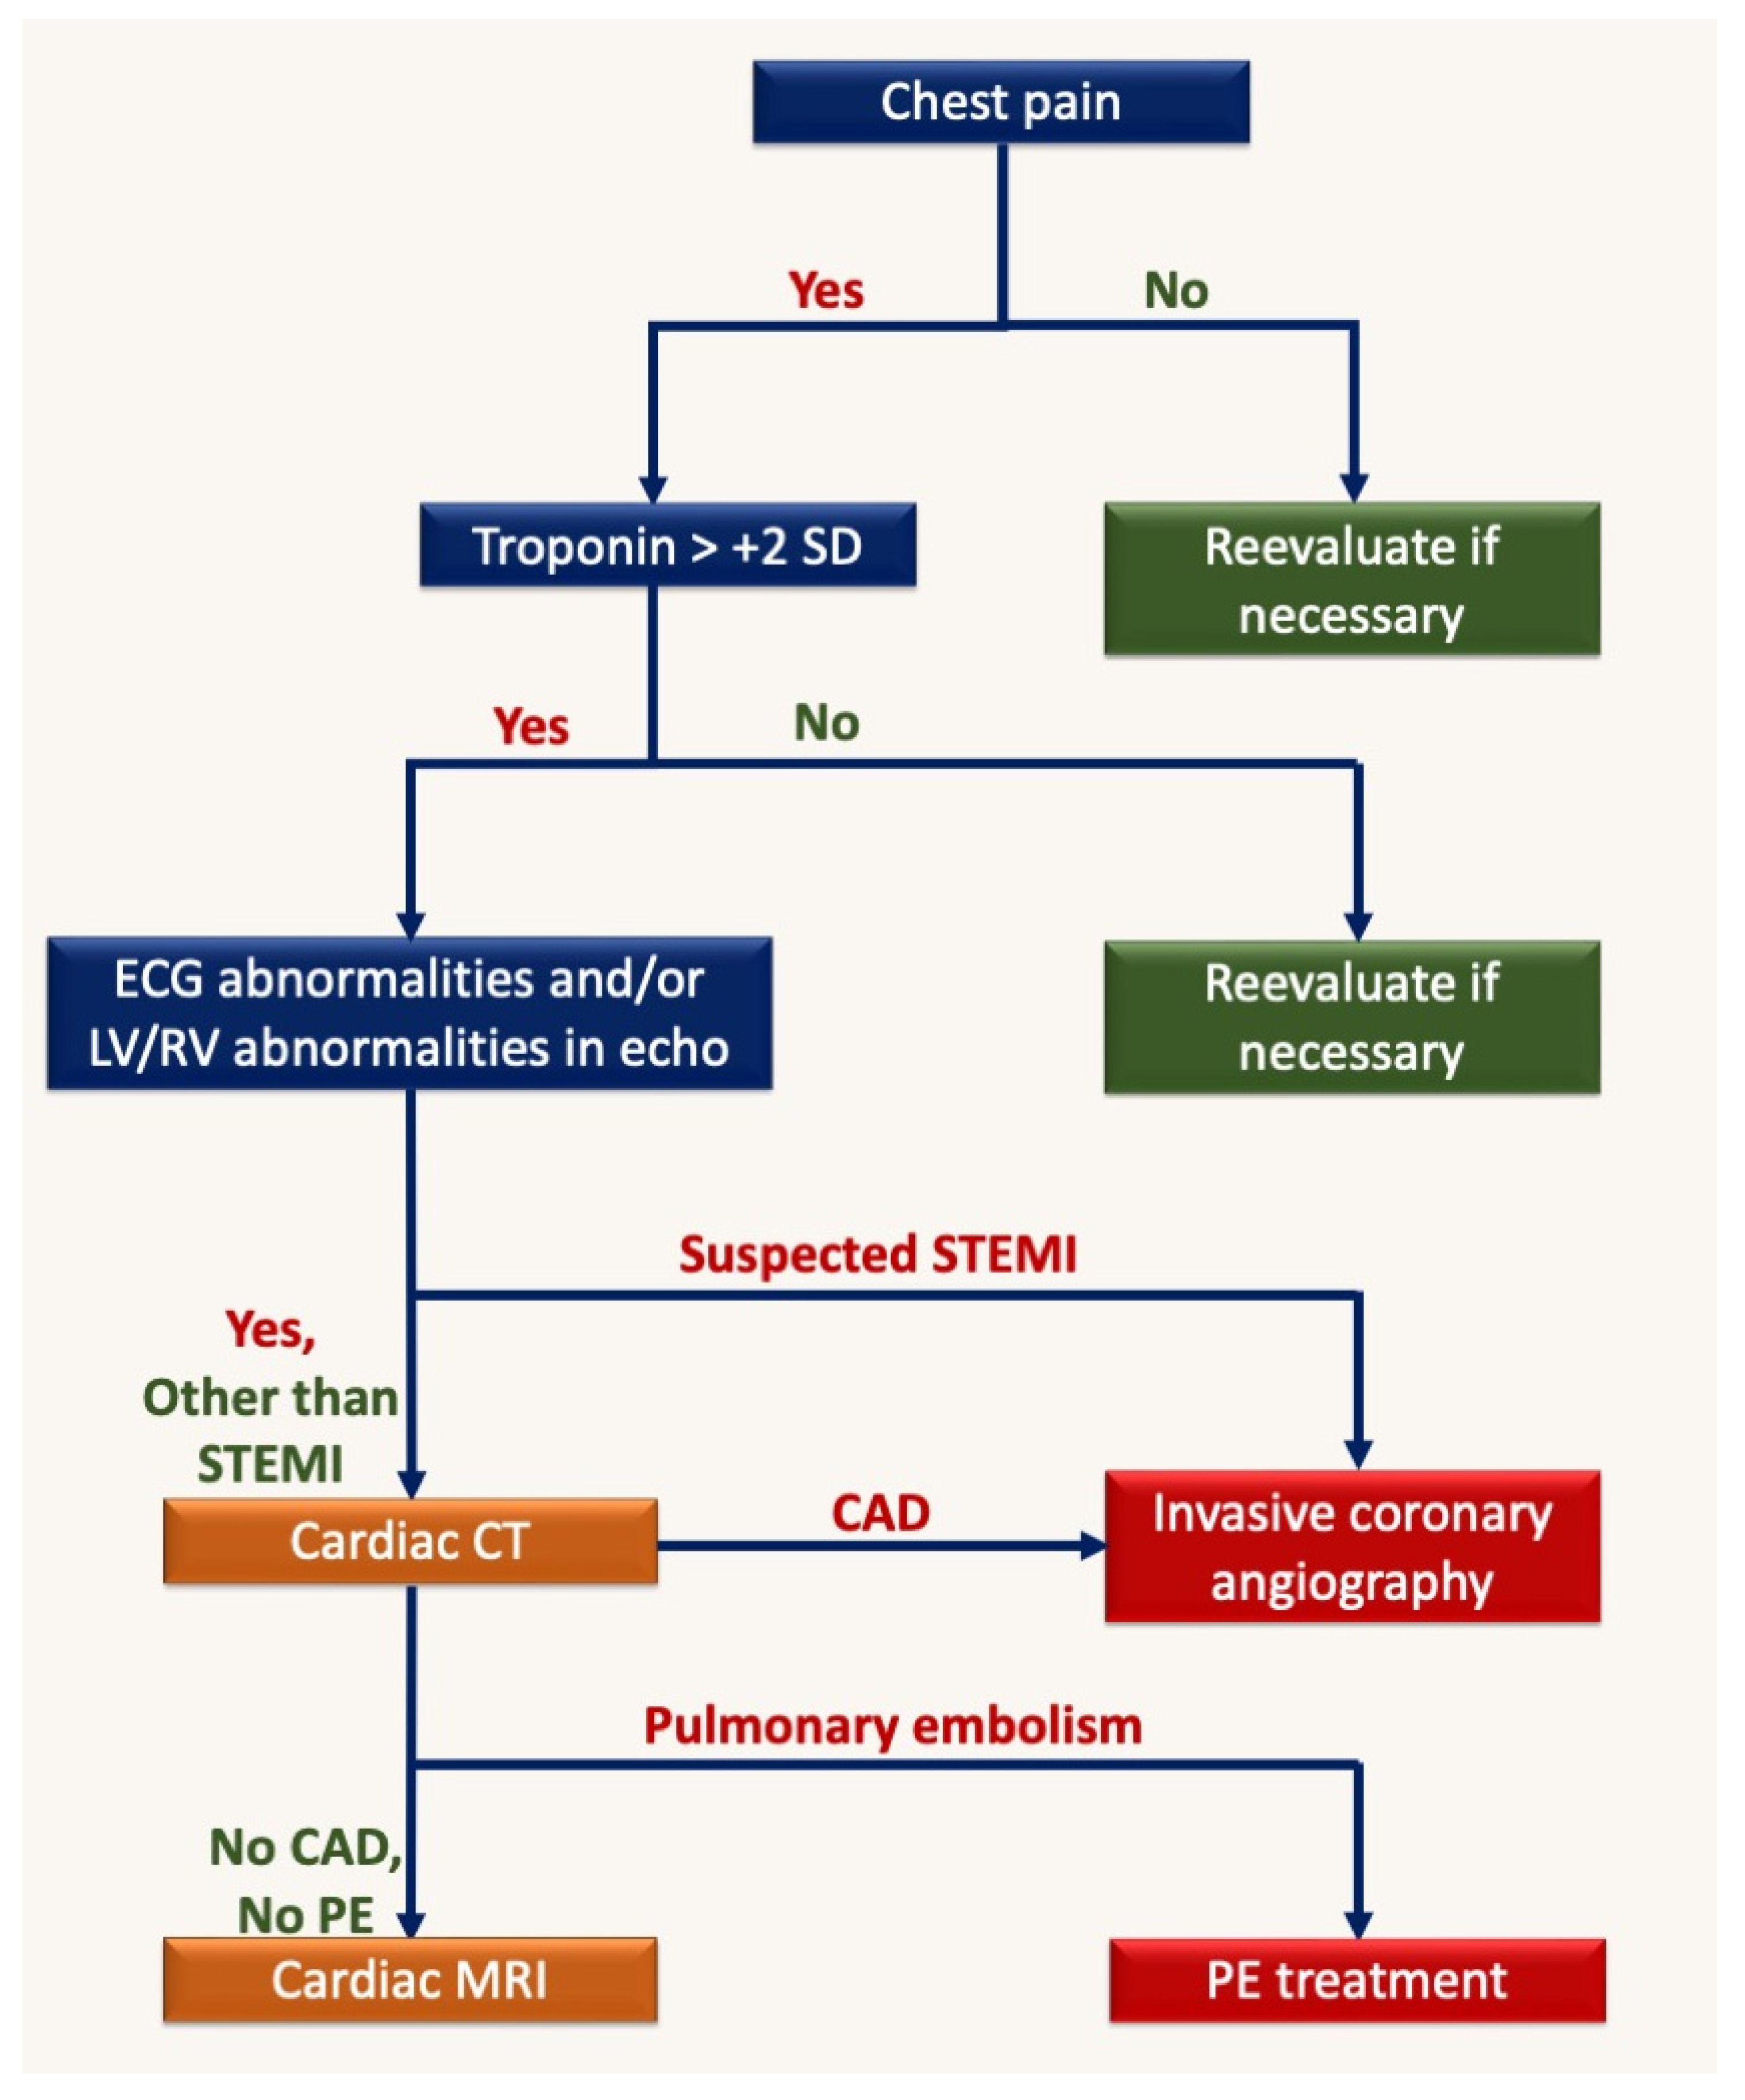

Abstract

:1. Introduction

3. Echocardiography

4. Cardiac Magnetic Resonance (CMR)

5. Computed Tomography (CT)

- Cosyns, B.; Lochy, S.; Luchian, M.L.; Gimelli, A.; Pontone, G.; Allard, S.D.; De Mey, J.; Rosseel, P.; Dweck, M.; E Petersen, S.; et al. The role of cardiovascular imaging for myocardial injury in hospitalized COVID-19 patients. Eur. Heart J. Cardiovasc. Imaging 2020, 21, 709–714. [Google Scholar] [CrossRef] [PubMed]